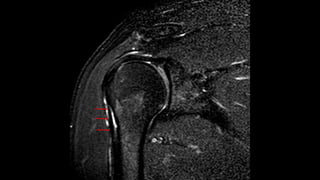

O documento aborda lesões no ombro, dividindo-as por faixas etárias: fraturas de clavícula em crianças, luxações em adultos e fraturas do úmero proximal em idosos. Descreve também técnicas de avaliação radiográfica e suas variações, incluindo incidências específicas para diagnóstico. Além disso, são mencionados métodos de imagem alternativos para a avaliação de partes moles e condições articulares.